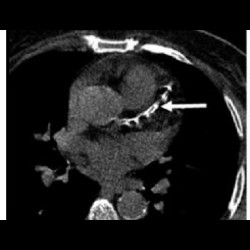

SYNTAX Score

SYNTAX Score in Patients with High Computed Tomography Coronary Calcium Score

SYNTAX Score

SYNTAX Score in Patients with High Computed Tomography Coronary Calcium Score